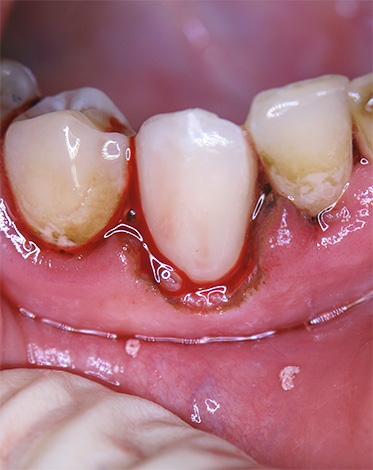

Molto spesso (in circa il 60-90% dei casi), negli anziani si sviluppa carie di cemento a causa di malattie gengivali di varia origine. Inoltre, nella maggior parte dei casi, si forma una tasca patologica tra la gengiva e il dente - un luogo di accumulo di vari microrganismi che non solo provoca la distruzione dell'attacco gengivale, che porta all'allentamento del dente, ma provoca anche lo scioglimento del cemento radicolare con un approfondimento della dentina radicale (streptococco).

- Carie cervicale o circolare. Se il processo carioso nella regione gengivale accede al cemento della radice del dente, si forma una sorta di "doppia" carie con due tipi di localizzazione: sopra la gomma e sotto la gomma. Qui, o una violazione dell'adattamento della gomma, che copre il collo del dente, o l'esposizione della radice per qualsiasi motivo gioca un ruolo.

- Violazione dell'igiene orale.Un costante accumulo di placca nella regione cervicale del dente o una corona di scarsa qualità senza un'igiene adeguata e regolare spesso porta alla gomma e alla carie subgengivale a causa di fattori cariogenici nella dissoluzione dello smalto dei denti e del cemento radicolare.